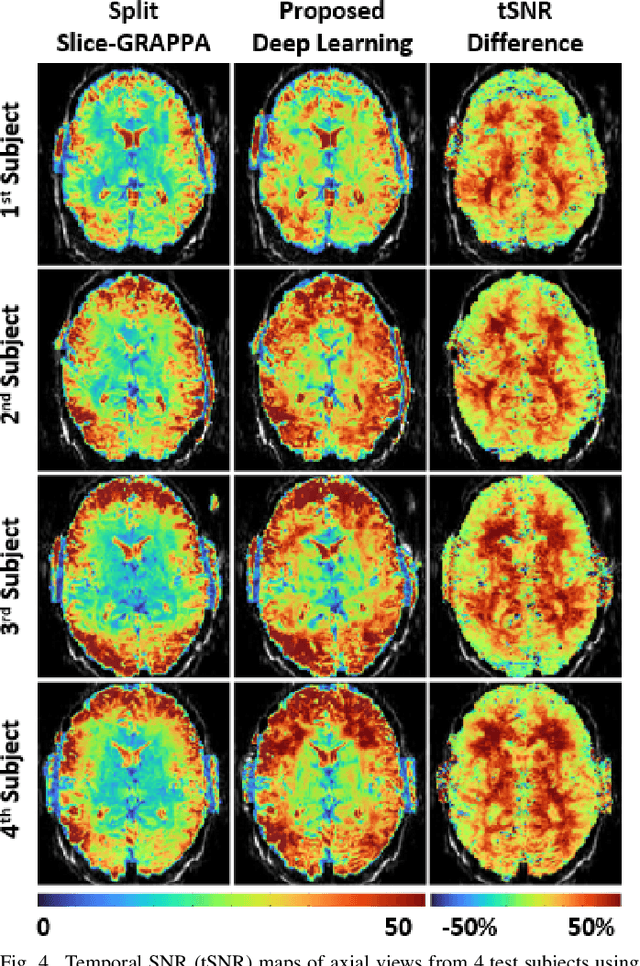

Functional MRI (fMRI) is commonly used for interpreting neural activities across the brain. Numerous accelerated fMRI techniques aim to provide improved spatiotemporal resolutions. Among these, simultaneous multi-slice (SMS) imaging has emerged as a powerful strategy, becoming a part of large-scale studies, such as the Human Connectome Project. However, when SMS imaging is combined with in-plane acceleration for higher acceleration rates, conventional SMS reconstruction methods may suffer from noise amplification and other artifacts. Recently, deep learning (DL) techniques have gained interest for improving MRI reconstruction. However, these methods are typically trained in a supervised manner that necessitates fully-sampled reference data, which is not feasible in highly-accelerated fMRI acquisitions. Self-supervised learning that does not require fully-sampled data has recently been proposed and has shown similar performance to supervised learning. However, it has only been applied for in-plane acceleration. Furthermore the effect of DL reconstruction on subsequent fMRI analysis remains unclear. In this work, we extend self-supervised DL reconstruction to SMS imaging. Our results on prospectively 10-fold accelerated 7T fMRI data show that self-supervised DL reduces reconstruction noise and suppresses residual artifacts. Subsequent fMRI analysis remains unaltered by DL processing, while the improved temporal signal-to-noise ratio produces higher coherence estimates between task runs.